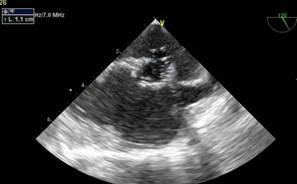

La reconstrucción 3D muestra un defecto alargado de 5 por 10 a 11 mm con presencia de membrana que lo tabica parcialmente, (Figura 6)